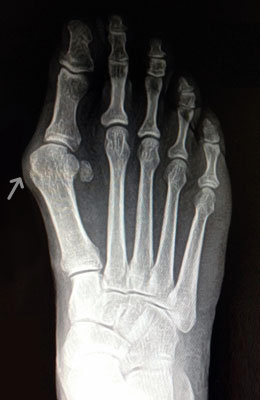

Before

Minimally Invasive Bunion Surgery before

After

Minimally Invasive Bunion Surgery after

Minimally Invasive Bunion Surgery featuring the miniBunon™ System and Tailors Bunionectomy

Melissa is a 32-year-old businesswoman who could not be off her foot post-surgery, yet she had a severely painful bunion. We performed our miniBunon™ System (our trademarked minimally invasive bunion surgery) and had a dramatic correction with no downtime. Melissa continued to work after her bunion surgery and was back in shoes and full activity at 5 weeks. Melissa could not believe the results of her Bunionectomy resulting in no bony bump, no scar and amazing motion. “After” picture taken immediately following surgery. Note the bunion and bunionette (Tailor’s bunion) in the before picture.